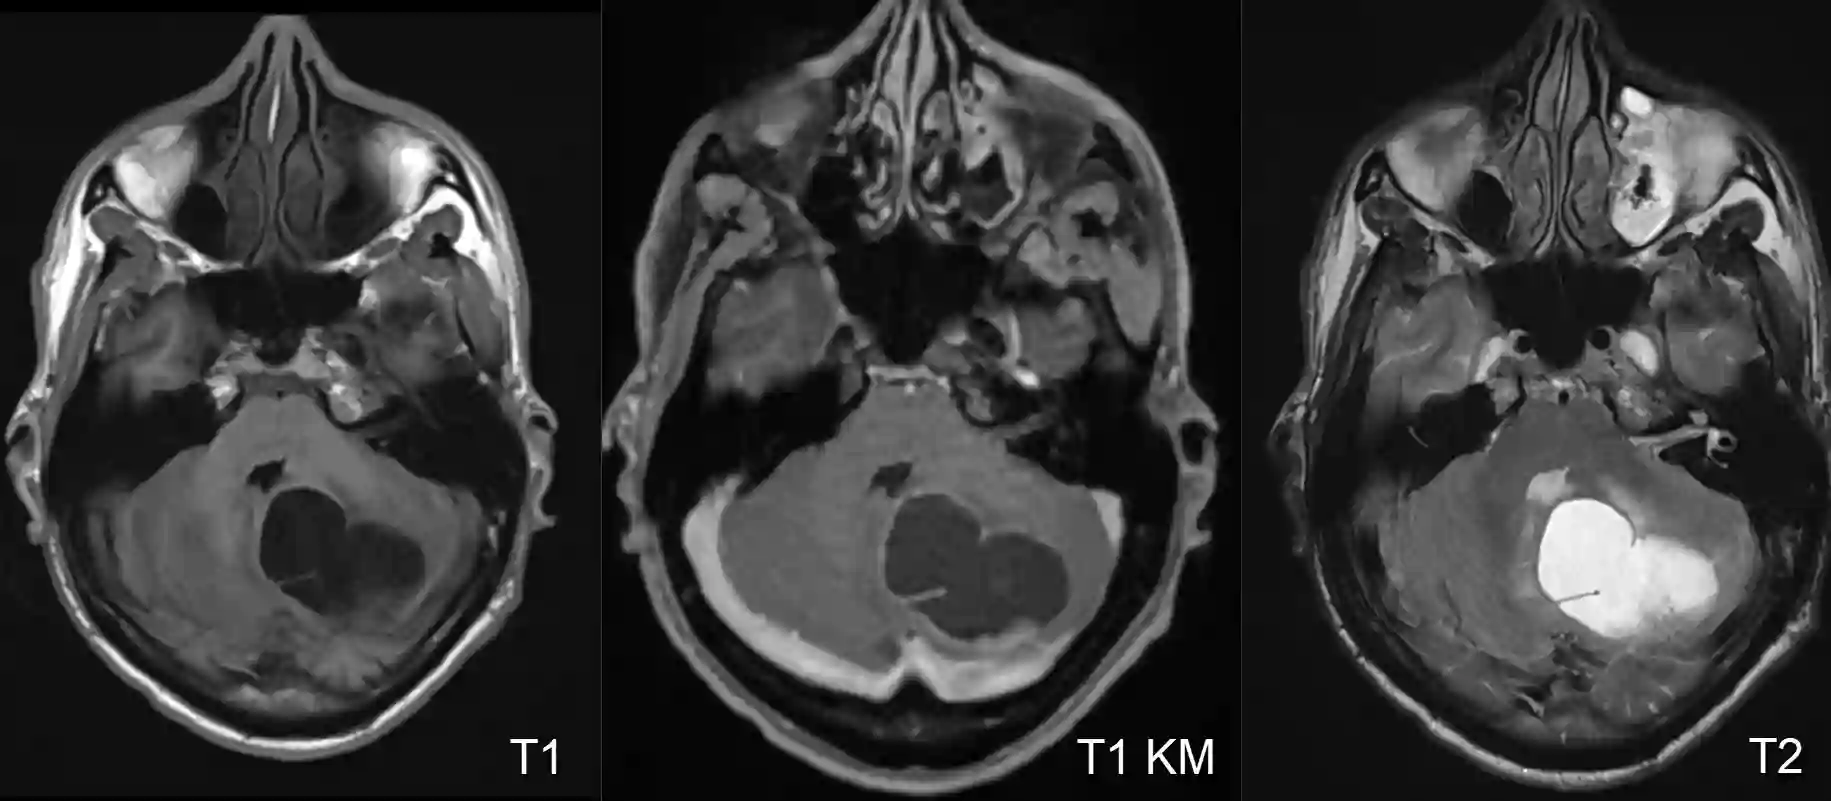

Bildgebung

Der Goldstandard in der Bildgebung von Hämangioblastomen ist die MRT Bildgebung. In einer digitalen Subtraktionsangiographie zeigt sich häufig ein stark vaskularisierter Nodulus mit Feedergefäßen, welcher suggestiv für ein Hämangioblastom ist.